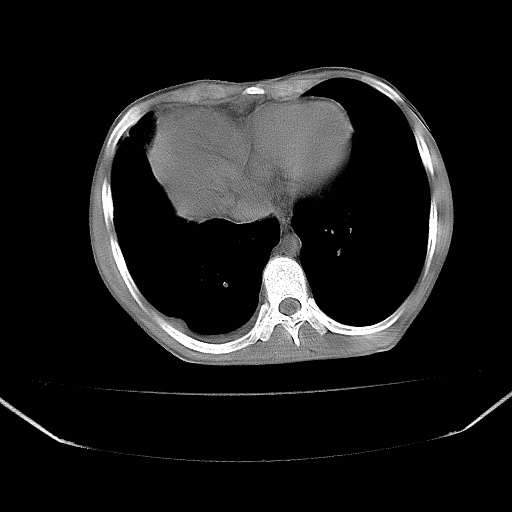

以下是引用zjzjr在2008-7-20 12:57:00的发言:[br]考虑为生殖源性肿瘤(内胚窦瘤),侵袭性胸腺瘤可能性大;右侧少量胸腔积液。

以下是引用xinliheng001在2008-7-20 21:17:00的发言:[br]右纵隔巨大分叶状软组织均质密度肿块,右上肺叶受压明显,纵隔右移、胸膜受累有少量积液和结节样增厚。应增强扫描一定会有更具诊断价值的信息。

以下是引用xinliheng001在2008-7-20 21:17:00的发言:[br]右纵隔巨大分叶状软组织均质密度肿块,右上肺叶受压明显,纵隔右移、胸膜受累有少量积液和结节样增厚。应增强扫描一定会有更具诊断价值的信息。